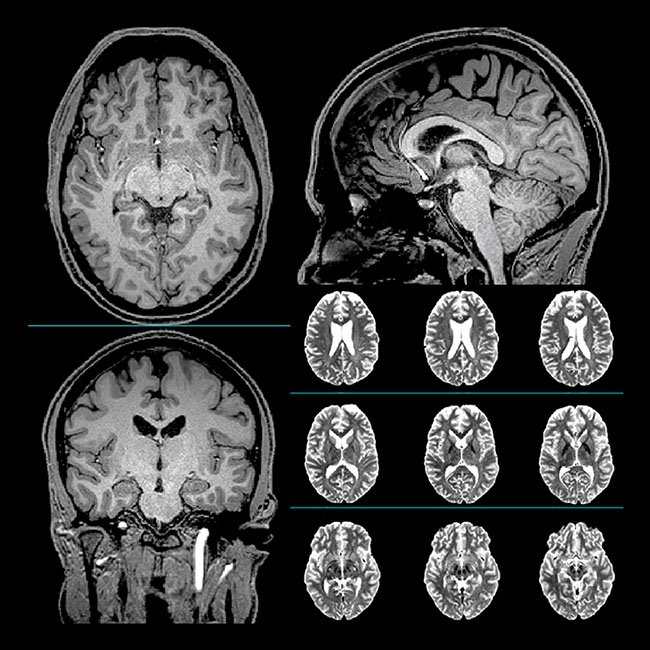

Indeed, the study provides significant evidence that PBM helps the brain to repair itself! Magnetic resonance imaging (MRI) was used to measure the growth of neurons. In addition to growth and repair of damage in the brain cells, the brain was observed to perform more efficiently.